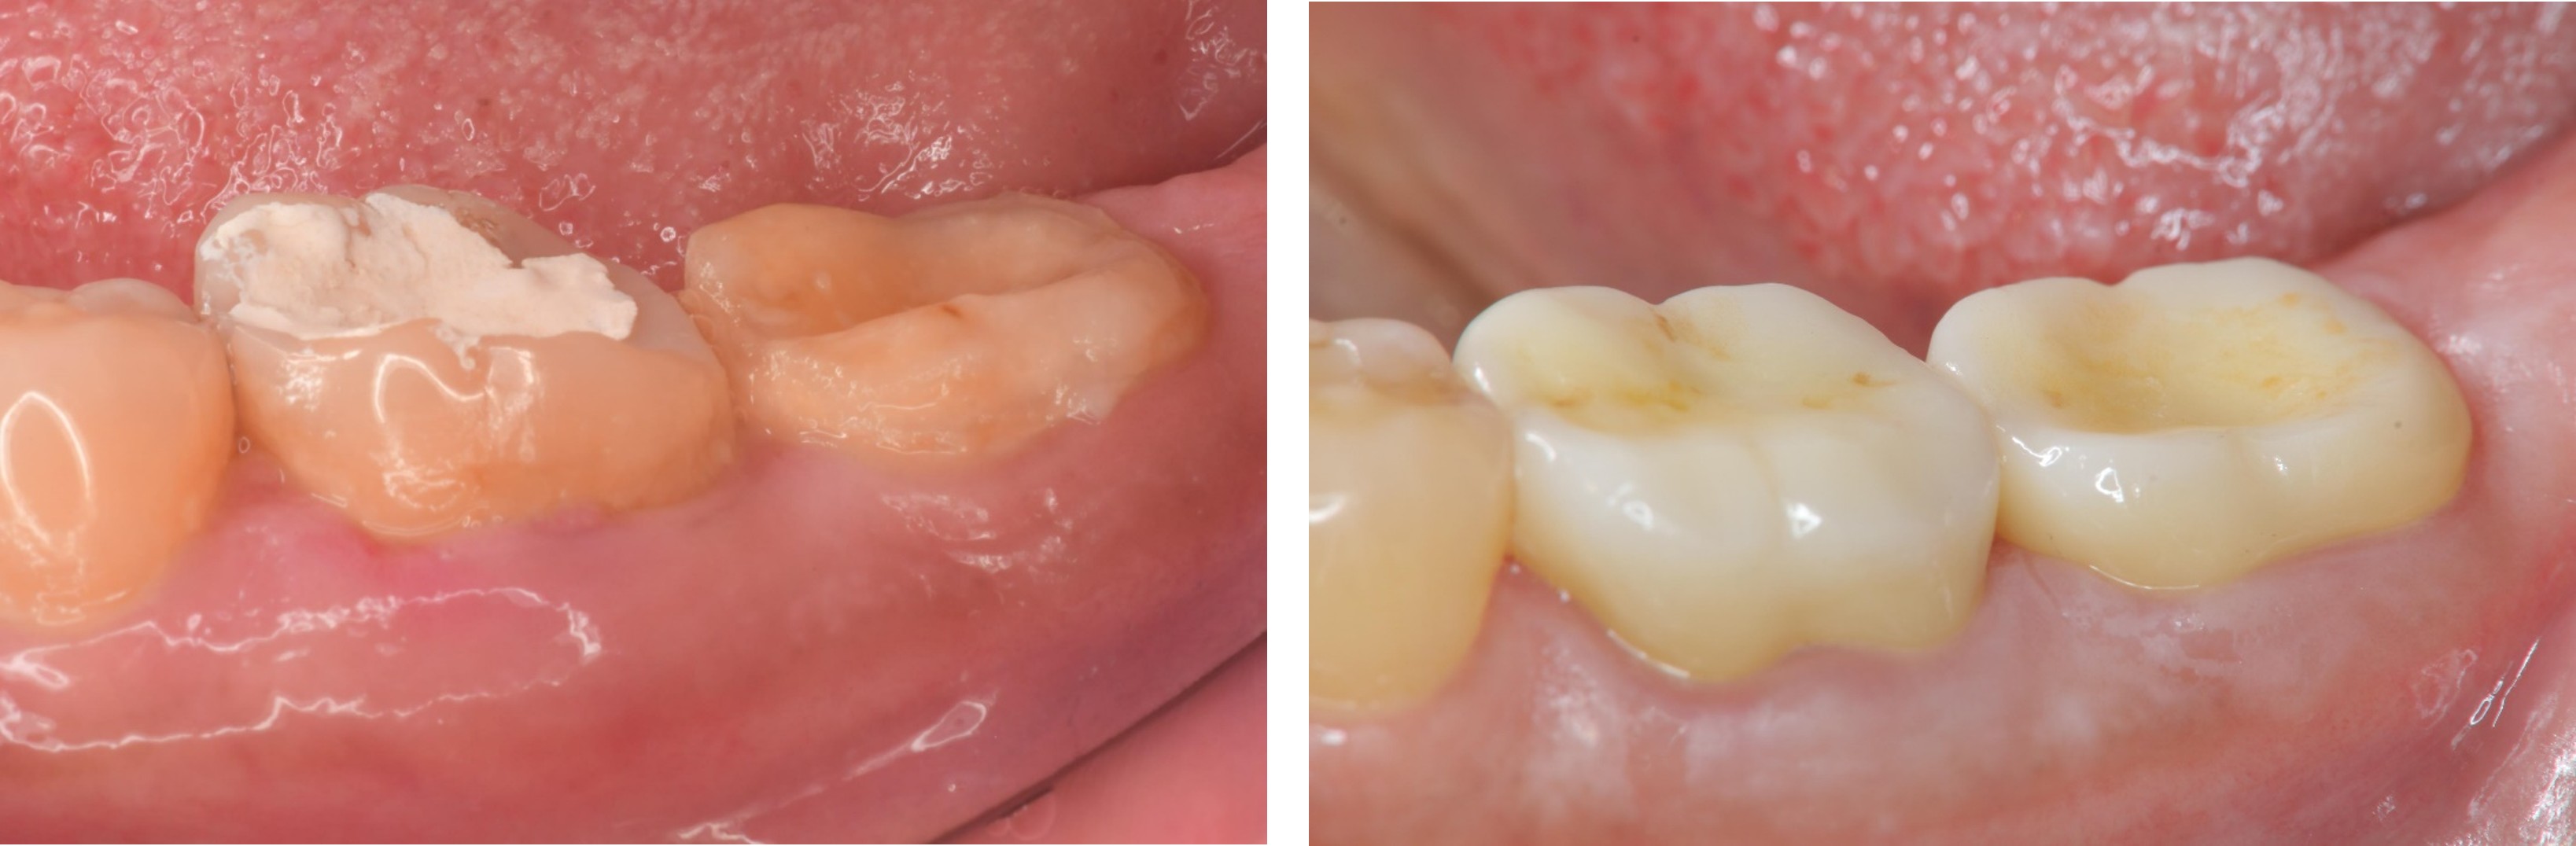

治療後,牙周咬合良好

治療後,密合度良好

術前、術後比較